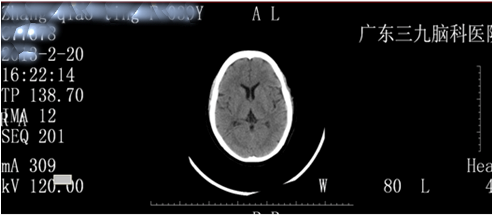

2:19行头颅CT平扫未见异常。(图一)

图一:治疗前头颅CT